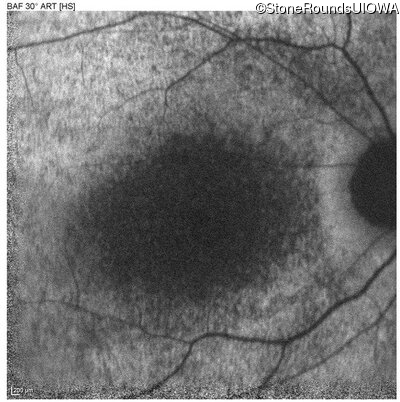

Age at visit: 6 years

OD OS

This 6 year old male first experienced a loss of visual acuity at age 5. His acuity was previously normal. He is otherwise healthy.